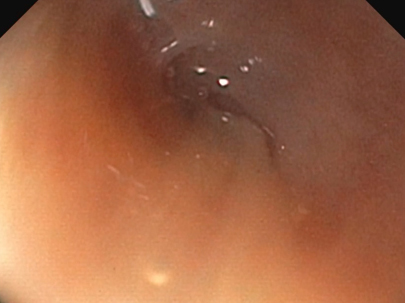

鼻腔内視鏡の様子:Jターン

鼻腔内視鏡の様子:内視鏡での狭窄部位